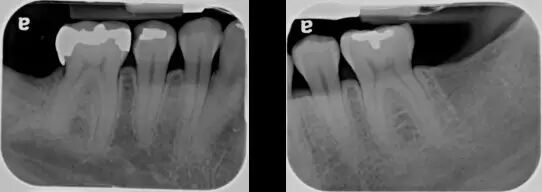

图 2 达到诊断质量的根尖片(X 光片取自笔者治疗过的病人)

图 3 诊断质量欠佳的根尖片(原因:牙合 面显示太多,说明 X 光片拍摄角度有问题,片子有变形)

要是碰巧根尖片没达到这个标准呢?那要看这是解剖原因造成的(有些患者无法忍受口腔里置放片子,会有恶心反应;或是腭部弧度过小、平坦,片子无法平行于牙长轴),还是拍片技术原因造成的建立信用评价和服务能力评审制度,有 利于加强对社会办医的管理,引导规范行医,提高管理水平。如果是技术原因造成的,需要提高拍片技术价格的制定首先要符合门诊的定位和定位群体的口腔健康消费心理。